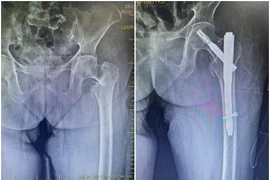

Biến chứng nguy hiểm do gãy liên mấu chuyển xương đùi

Phẫu thuật kết hợp xương ít xâm lấn điều trị gãy liên mấu chuyển xương đùi giúp người bệnh hồi phục nhanh, tránh biến chứng nguy hiểm.